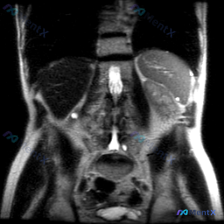

先看影像里的客观所见

- 肝脏、胆囊、胆道:肝实质信号均匀,胆囊是生理性高信号,胆道没看到明显扩张;

- 脾脏:报告写“形态尚可,实质信号未见明显异常”;

- 右侧肾区:有一个类圆形高信号,边界很清,信号和胆囊液差不多,典型的囊性表现;

- 其他:腹膜后没见肿大淋巴结,没有腹水,血管看起来也还行。